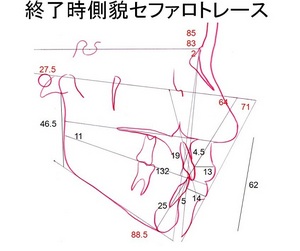

・上下顎前歯の前方傾斜も理想的に改善

・横顔評価の数値も大きく改善

終了時重ね合わせ評価①